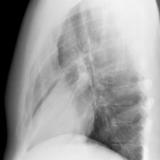

Case 2 Lateral

Date: 02/28/2004

Views: 3385